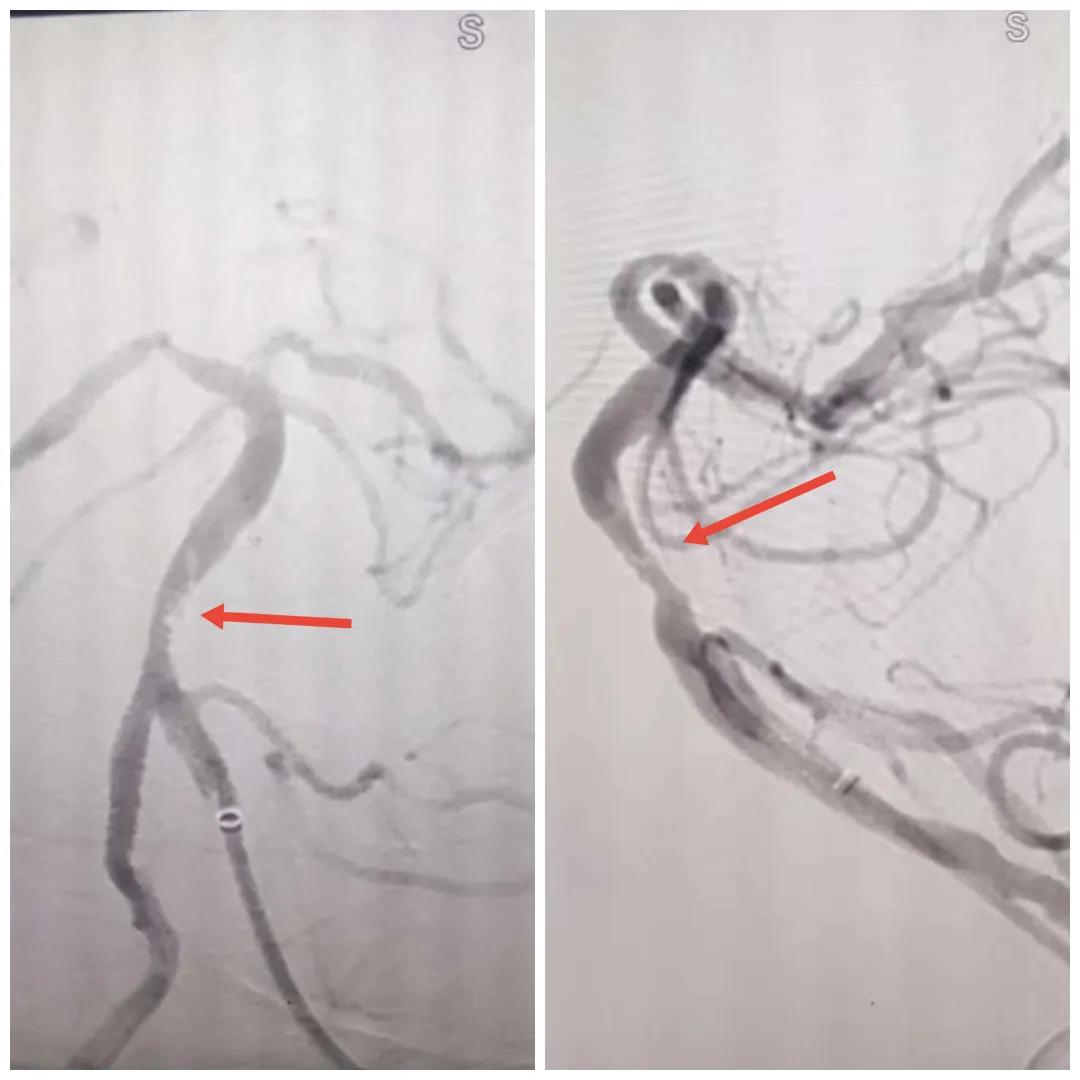

磁共振MRA提示基底動脈閉塞

在經(jīng)造影后,主刀醫(yī)生腦一科副主任楊慶堂發(fā)現(xiàn)患者基底動脈下段重度狹窄且狹窄段以遠(yuǎn)有大負(fù)荷血栓,其狹窄處考慮為動脈夾層,手術(shù)難度及風(fēng)險較大。楊慶堂副主任在彭壯副主任醫(yī)師的協(xié)助下運用spaceman(太空人)技術(shù),中間導(dǎo)管抵近血栓抽吸配合支架拉栓,成功開通血管。再次造影可見基底動脈管腔明顯增寬,遠(yuǎn)端血管顯影良好,且等待20分鐘后造影仍顯示血流通暢。楊慶堂副主任考慮到本次手術(shù)時間不宜過長,現(xiàn)患者基底動脈及分支前向血流維持良好,給予其抗栓藥物應(yīng)用后結(jié)束手術(shù),并建議患者3個月后復(fù)查造影,明確其基底動脈夾層情況。

造影可見血管夾層和大量血栓形成

取栓后血管管腔增寬,前向血流良好